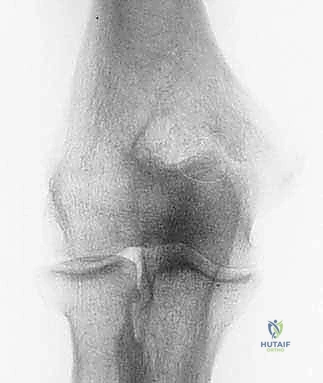

* الأشعة السينية (X-rays): ضرورية جداً لرؤية النتوءات العظمية (Osteophytes) في الناتئ المرفقي، وتضييق مساحة المفصل.

* التصوير بالرنين المغناطيسي (MRI): يُستخدم لتقييم الأنسجة الرخوة، وتحديداً حالة الرباط الجانبي الزندي (UCL)، والكشف عن وذمة نخاع العظم (Bone Marrow Edema) الناتجة عن الاصطدام المتكرر، وتقييم حالة الغضاريف.

* الأشعة المقطعية (CT Scan): في بعض الحالات المعقدة، تُستخدم لبناء نموذج ثلاثي الأبعاد للمفصل للتخطيط الجراحي الدقيق قبل إدخال المنظار.